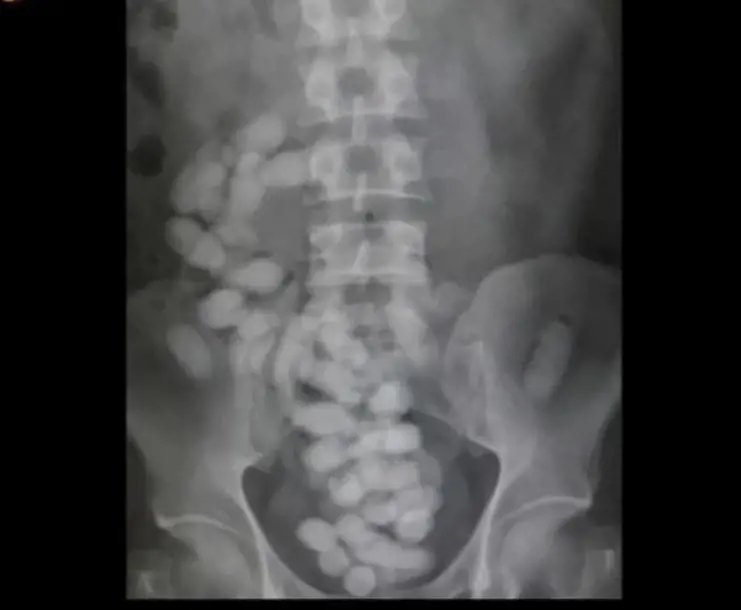

Decisi ad eseguire un’ulteriore verifica, i finanzieri hanno chiesto ed ottenuto dal pubblico ministero di turno di poter trasportare lo straniero al policlinico di Monserrato, dove il personale medico si è occupato di eseguire gli esami radiodiagnostici di routine.

Le indagini cliniche hanno confermato i sospetti degli uomini della finanza. Lo straniero trasportava ben 31 ovuli termosaldati nel suo intestino. Una volta espulsi, gli involucri sono risultati contentere 314 grammi di eroina. La droga è stata sequestrata, così come un cellulare e la scheda sim in esso contenuta, che sarà utile per le indagini.